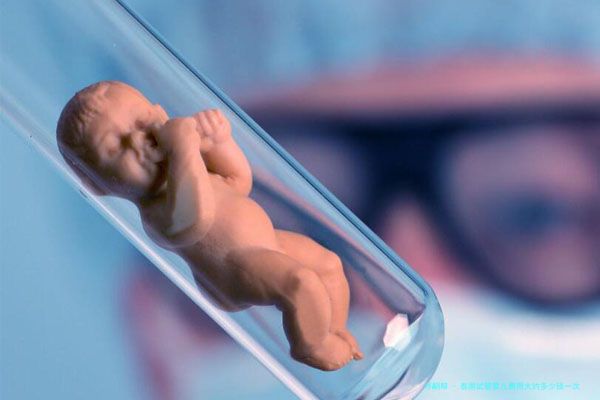

泰国试管婴儿近年来备受国内外夫妻的注意,作为西北亚医疗水平领跑国家,其试管婴儿技术成熟、服务优质、费用相对适当,成为许多要想实现生育梦想的家庭选择靠前。那么,泰国试管费用大约多少钱1次呢?

起先,须要明白的是,泰国试管婴儿费用并非变化无穷,会根据个人的具体情况有所差距。一般来说,囊括促排卵药物、卵子 Retrieval、胚胎移植等步调的总费用在十五万至二十万元块钱左右。

泰国试管婴儿成功率在50%-70%之间,也是抉择它的主要原因其中之一。许多夫妻选择到泰国进行试管婴儿,不仅是因为医疗技术的先进特性,还因为它相对成熟的相关服务体系,能够为病患提供从咨询、检查、治疗到返国后的各项支持。